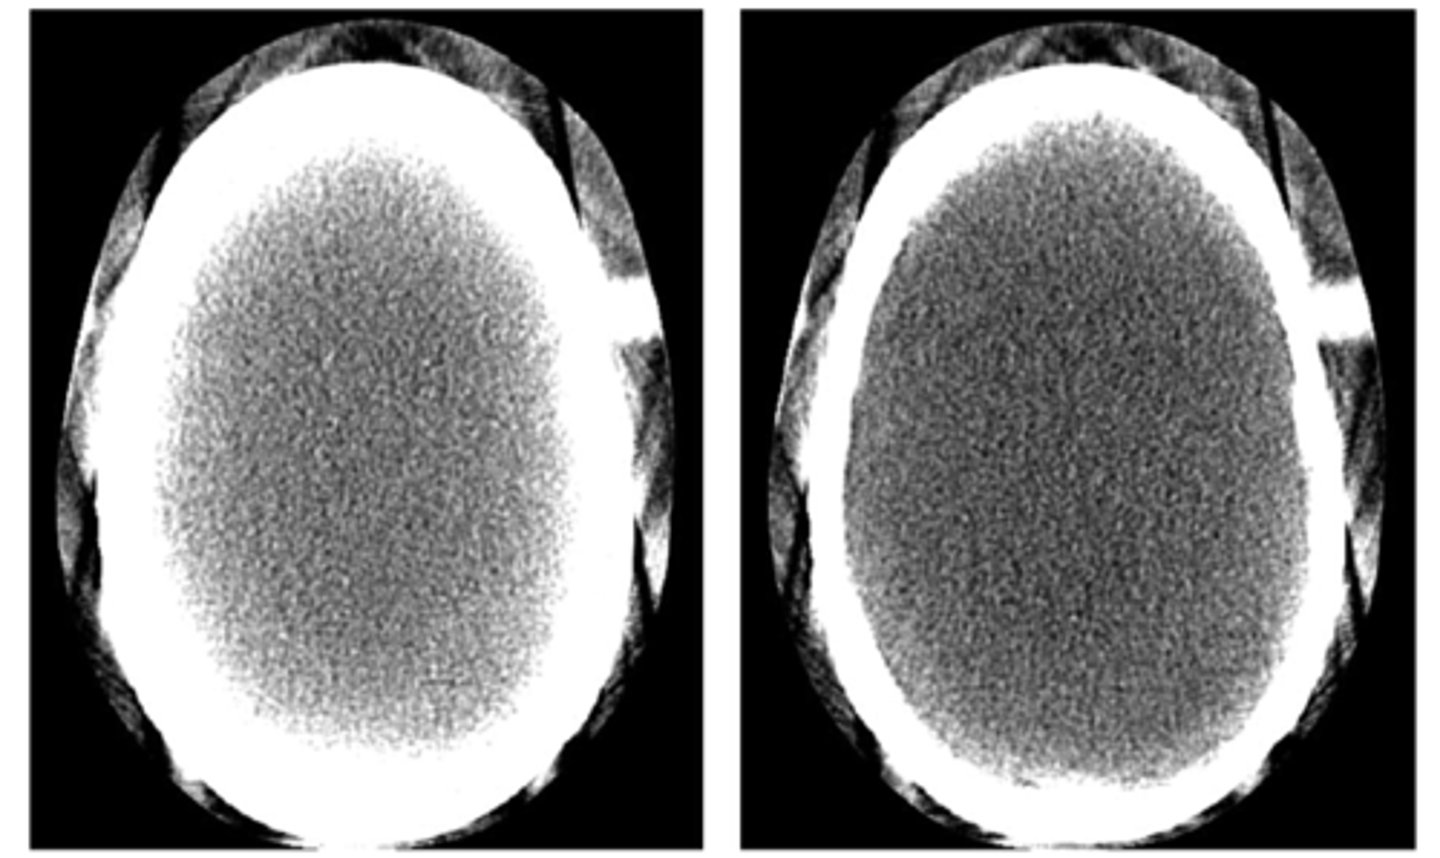

What is beam hardening?

what are the two types of beam hardening artifact?

how do you compensate for it?

1) as the X-ray beam passes through an object, lower energy photons are removed (like filtration!) leaving a "harder beam" of high energy photons. This causes two artifacts:

2) Cupping: the center of a round object is darker than the periphery due to hardening of the beam 360 degrees around the object. happens in the head

3) Streak: these are dark bands that occur in between two dense objects - nearly all the photons are removed in a line between the two objects

4) fixes:

A) Filtration: pre-hardening the beam to remove low energy photons

B) Calibration: using a phantom to set a compensated mA/kVp

C) Correct software: iterative reconstruction may help

D) Avoidance: tilting the gantry of positioning the patient to avoid areas that may cause hardening.

<p>1) as the X-ray beam passes through an object, lower energy photons are removed (like filtration!) leaving a "harder beam" of high energy photons. This causes two artifacts:</p><p>2) Cupping: the center of a round object is darker than the periphery due to hardening of the beam 360 degrees around the object. happens in the head</p><p>3) Streak: these are dark bands that occur in between two dense objects - nearly all the photons are removed in a line between the two objects</p><p>4) fixes:</p><p>A) Filtration: pre-hardening the beam to remove low energy photons</p><p>B) Calibration: using a phantom to set a compensated mA/kVp</p><p>C) Correct software: iterative reconstruction may help</p><p>D) Avoidance: tilting the gantry of positioning the patient to avoid areas that may cause hardening.</p>